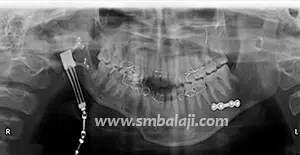

The goal of treatment in hemifacial microsomia is to elongate the deficient jaw bone to restore facial symmetry and correct the slanting bite (occlusion). To achieve this, an advanced and effective treatment technique is distraction osteogenesis. This is a new technique for regenerating new bone by slow, progressive stretching of the bone, without requiring a bone graft.

The jaw bone on the deficient side is cut. A sophisticated device called distractor is placed such that the two arms of the device are fixed to the two segments of jaw bone. After a few days, a screw attached to the distractor is turned gradually, ideally at a rate of 1 mm per day. When this is done, the two cut segments move apart and new bone is formed in the resultant gap. After the new bone is stabilized, the distractor device is removed.

Subsequently, the jaw bone is lengthened to the desired amount correcting the asymmetry of the face. This is a powerful tissue engineering technique for generating unlimited bone.